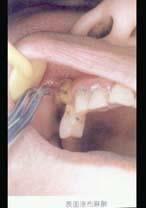

7岁患儿下颌乳中切牙松动Ⅲ度、拔除时宜采用 ( )

- A.2%普鲁卡因浸润麻醉

- B.2%丁卡因表面麻醉

- C.2%利多卡因浸润麻醉

- D.2%利多卡因阻滞麻醉

- E.2%普鲁卡因阻滞麻醉

正确答案

B